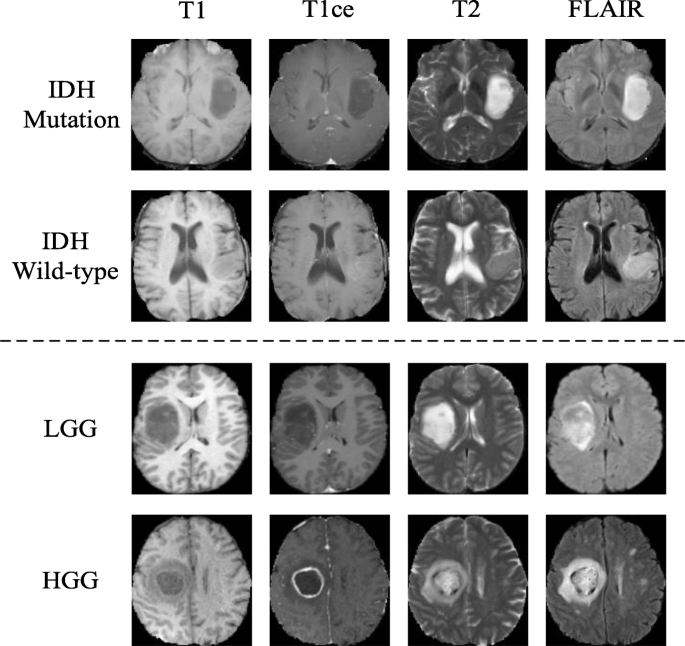

Hello sir i am pg student and doing project on an analysis of radiology reports by using svm please help me regarding my project.how to run image features and all send me the matlab code vipulsawake@gmail.com. World health organization (who) updates official classification of tumors of the central nervous system. Embryonal tumors of the brain and other organs (cerebellar medulloblastoma, adrenal neuroblastoma, occur predominantly in children.

We review brain tumor radiologic studies (eg, imaging interpretation) through computational second, recent breakthroughs in deep learning with applications in radiology, such as lung nodule. The 2016 world health organization classification of tumors of the central nervous system is both a conceptual and practical advance over its 2007 predecessor. A listing of most of the tumors that occur in the brain or its surrounding structures is presented here. Primary brain tumors are typically seen in a single region, but some.